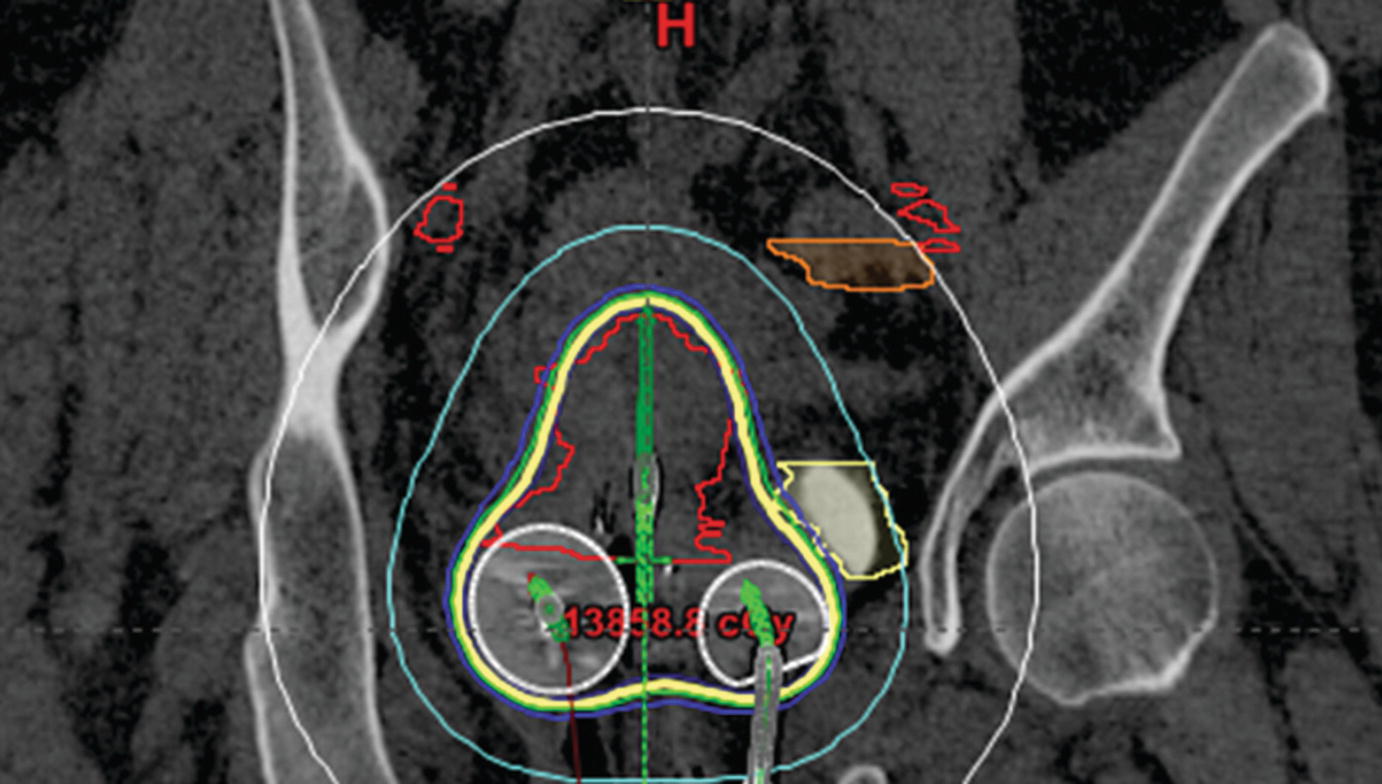

Purpose To develop a knowledgebased voxelwise dose prediction system using a convolution neural network for highdoserate brachytherapy cervical cancer treatments with a tandemandovoid (T&O) applicator Methods A 3D UNET was utilized to output dose predictions using organatrisk (OAR), highrisk clinical target volume (HRCTV), and possible source locations A sample of previous T&O. Do you add an IMRT boost with possibly vaginal brachytherapy?. Purpose To develop a knowledgebased voxelwise dose prediction system using a convolution neural network for highdoserate brachytherapy cervical cancer treatments with a tandemandovoid (T&O) applicator Methods A 3D UNET was utilized to output dose predictions using organatrisk (OAR), highrisk clinical target volume (HRCTV), and possible source locations A sample of previous T&O.

These patients received external beam radiation therapy delivered to 450 to 504 Gy in 25–28 fractions Intracavitary brachytherapy delivered in the T/O approach was given in four–five fractions in doses of 55–7 Gy per fraction All patients had MRI for brachytherapy planning at time of the first T/O from which HRCTV was created. Fortytwo percent of women were estimated to have inadequate tumor coverage with T O brachytherapy The GTVTinit volume and dimensions (superiorinferior, leftright, anteriorposterior) on MRI1 were all important predictive factors of inadequate coverage on multivariate analysis. What is your approach to a cervical SCC patient in which you're unable to properly place a T&O, due to obliterated cervical os, after completion of EBRT?.

Comparison Of A Conventional And B Volume Optimized T O Plans The Download Scientific Diagram